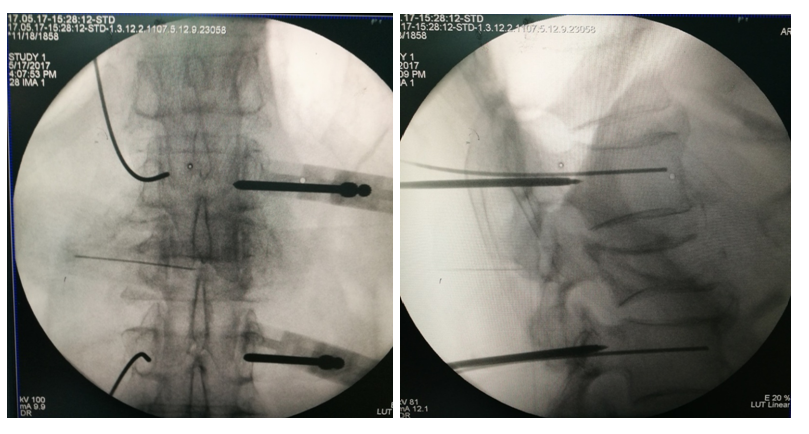

手术治疗

术后影像学

手术治疗:T10-T12棘突椎板切除;T11 截骨后凸矫形;T9-L1椎弓根固定,均为骨水泥螺钉,安放横联两根;T10/11及各椎板后方大量植异体骨及自体骨。

术中透视